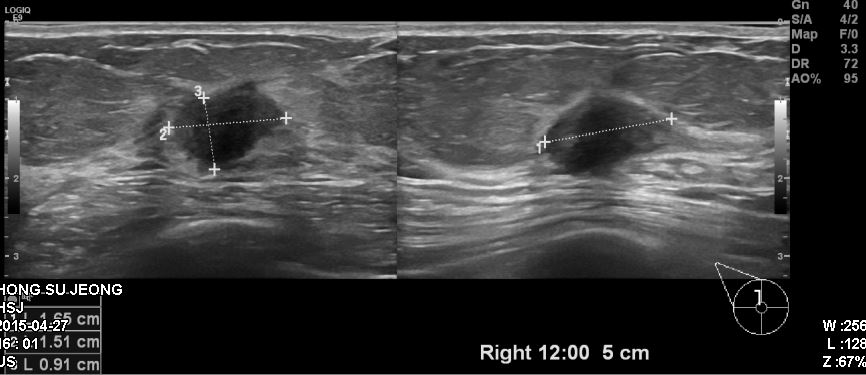

건강검진상 이상 소견으로 내원하신 50대 여성분으로 우측 침윤성유관암 진단되었습니다.